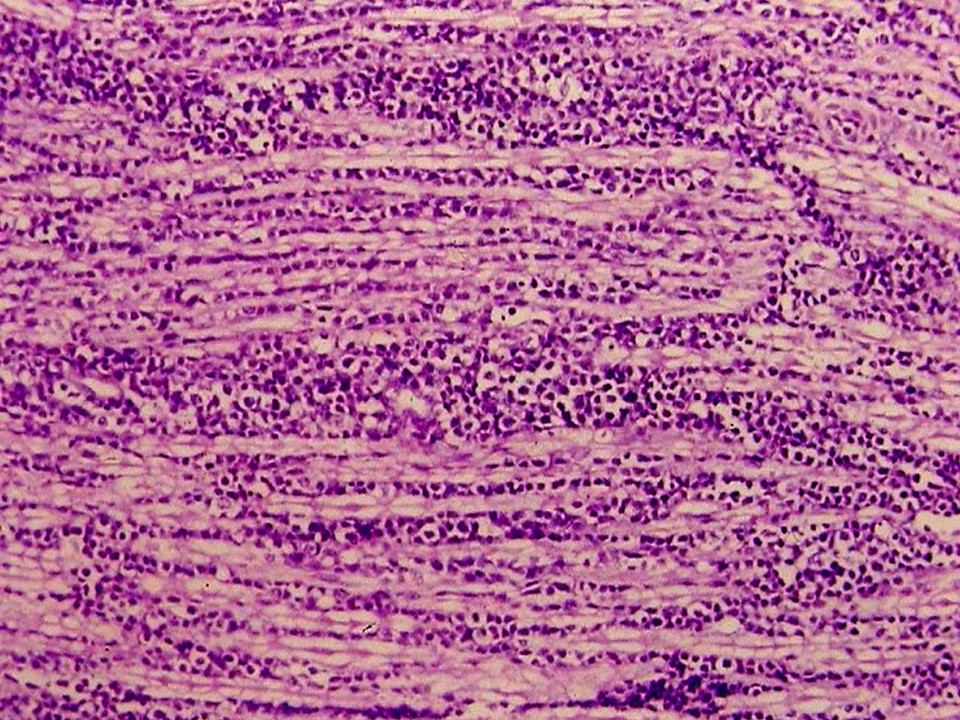

疾病中文名稱:馬立克病

疾病英文名稱:Marek's disease

作者:蔡信雄教授